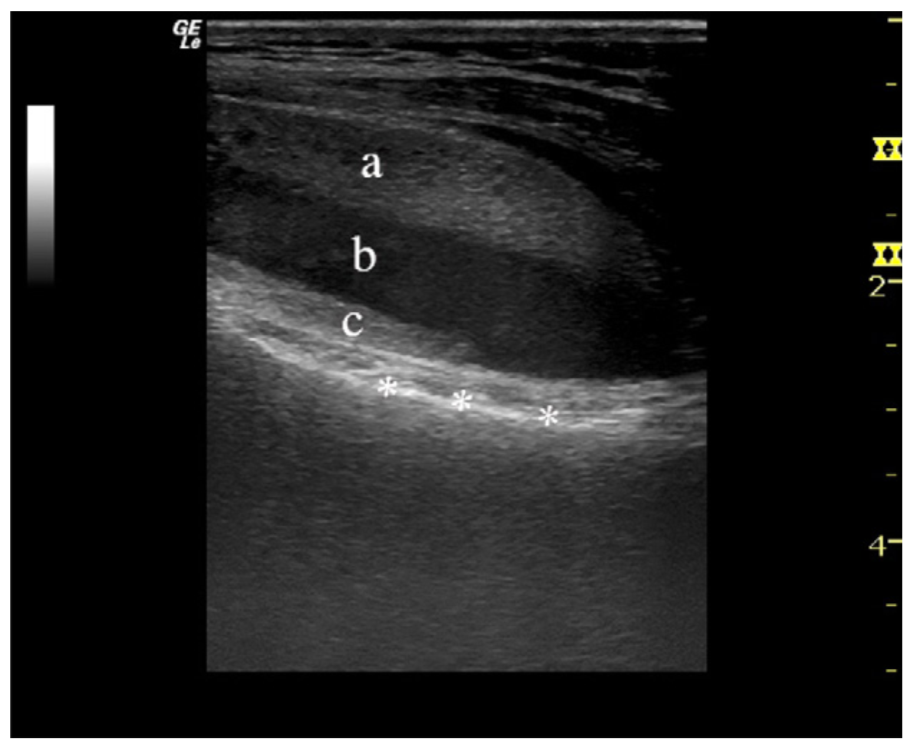

病例3一例膝关节外伤患者,在膝关节侧位X线上,积脂血症并不明显。